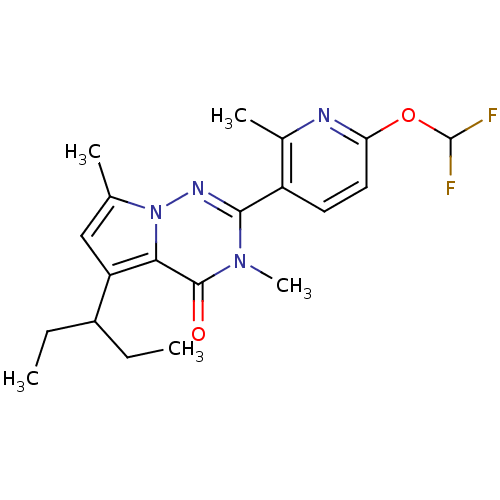

TargetCorticotropin-releasing factor receptor 1(Homo sapiens (Human))

Dupont Pharmaceuticals

Curated by ChEMBL

Dupont Pharmaceuticals

Curated by ChEMBL

Affinity DataEC50: 0.300nMAssay Description:Antagonist activity at human CRF1 receptor expressed in CHO-K1 cells assessed as CRF-stimulated cAMP accumulation by enzyme immunoassayMore data for this Ligand-Target Pair

Affinity DataEC50: 0.420nMAssay Description:Antagonist activity at CRF-R1 in mouse AtT-20 cells assessed as inhibition of human CRF induced cAMP accumulation after 30 mins by radioimmunoassayMore data for this Ligand-Target Pair

Affinity DataEC50: 0.440nMAssay Description:Antagonist activity at CRF-R1 in mouse AtT-20 cells assessed as inhibition of human CRF induced cAMP accumulation after 30 mins by radioimmunoassayMore data for this Ligand-Target Pair

Affinity DataEC50: 0.450nMAssay Description:Antagonist activity at CRF-R1 in mouse AtT-20 cells assessed as inhibition of human CRF induced cAMP accumulation after 30 mins by radioimmunoassayMore data for this Ligand-Target Pair